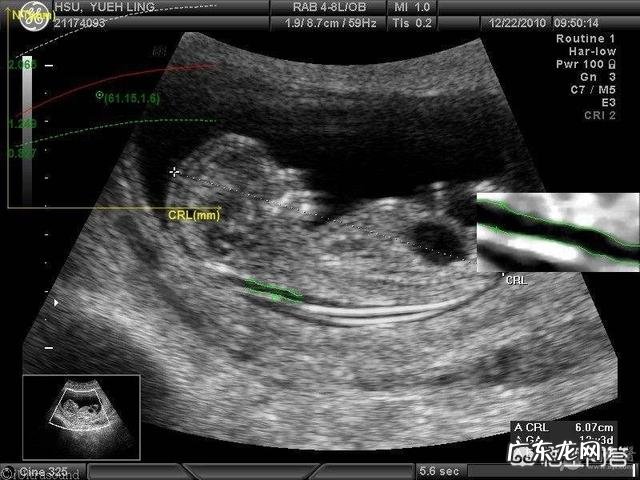

怀孕3个月,此时头臀径长月61mm,足长9mm,胎儿体重大概14g 。主要的外观特点:肠管退到腹腔内,早期的指甲发育 。宝宝的四肢关节已经可以活动了 。至于吞咽运动,解小便等技能还在学习中 。

总结,怀孕3个月的宝宝已经成形,体重大概14克左右,头臀径61mm,孕早期的头臀径是评估胎儿孕周的一个重要指标 。祝好孕 。